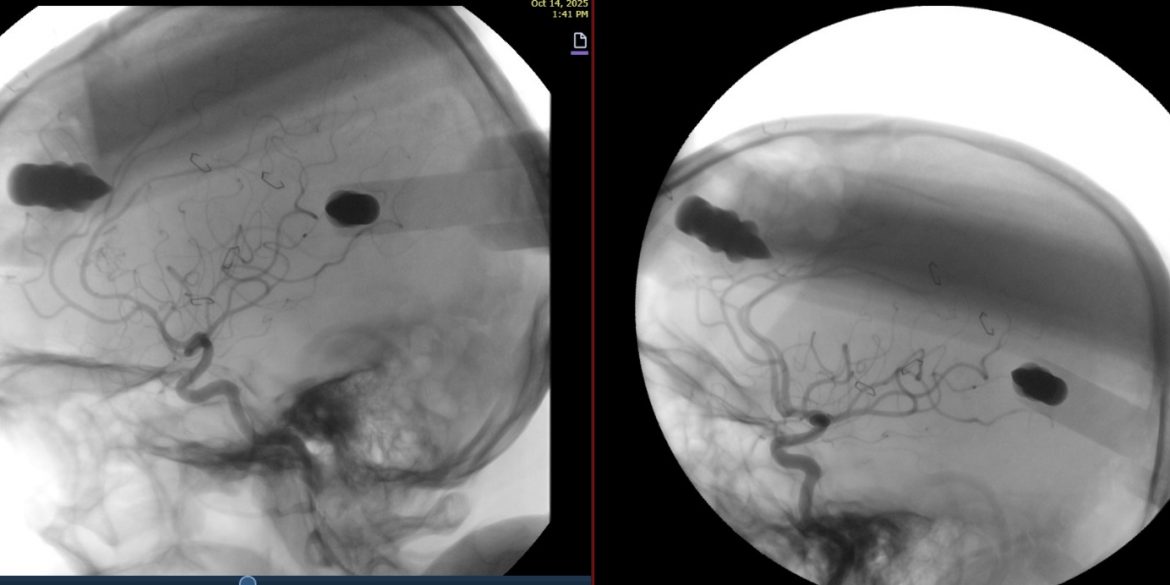

وبعد إجراء قسطرة تشخيصية للدماغ، تبيّن وجود تشوّه شرياني وريدي (AVM) بالقرب من البطينات في عمق الدماغ، حيث خضع المريض لعملية استئصال التشوّه الدماغي، مع استخدام القسطرة الدماغية أثناء العملية للتأكد من إزالة التشوّه بشكل كامل دون حدوث أي مضاعفات، وقد تماثل المريض للشفاء وغادر المستشفى بصحة جيدة.

وتُعد هذه الحالة إنجازًا طبيًا جديدًا لفريق جراحة المخ والأعصاب في مستشفى الدرعية، يعكس كفاءته العالية وقدرته على استخدام أحدث التقنيات التشخيصية والجراحية لعلاج التشوّهات الشريانية الوريدية الدماغية بدقة وأمان.

مستشفى الدرعية ينجح في استئصال تشوّه شرياني وريدي في عمق الدماغ بنجاح